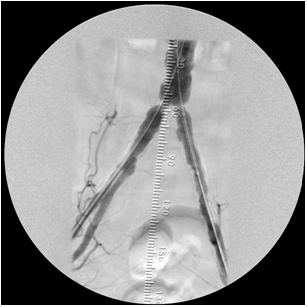

The images below illustrate such a problem. This patient in addition to having irregular chunks of calcium narrow his aorta has significant narrowing of the origins of his common iliac arteries (ostial stenosis), which along with the narrowings above and below them diminished the amount of blood reaching the patient’s feet from the aorta, causing symptoms.

By simultaneously deploying a stent across each common iliac ostial narrowing, I corrected the problem, delivering more blood into the patient’s feet. The first image shows the narrowings before the stents were deployed; the second image displays the process of stent deployment; the third image was taken after I landed the stents.